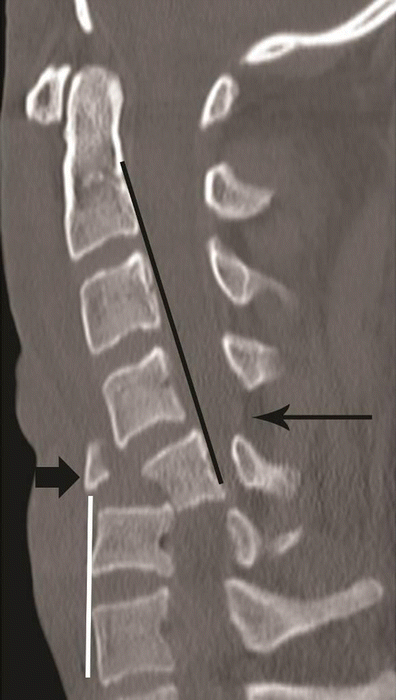

Flexion teardrop fracture. Sagittal CT image of cervical spine in a young patient following vehicular accident shows wedging of C5 vertebral body with an oblique coronal fracture of the anterior third of the vertebral body, dividing the C5 in to a smaller anterior triangular fragment (short arrow) and a large posterior segment. Retrolisthesis of the C5 vertebral body on C6 behind the fracture line and retropulsed C5 keeping alignment with the cranial C4 vertebral body—suggested by non-interrupted posterior vertebral line (black line), while triangular fragment keeping alignment with the caudal C6 vertebra—suggested by non-interrupted anterior spinal line (white line). Distraction of posterior column is suggested by widening of interspinous/interlaminar space at C4–C5 (long arrow). Facet joint subluxation was seen on the parasagittal images (not shown)